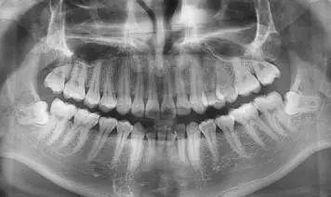

专家介绍说,拔牙之后为避免凝血组织的破坏,专家建议拔牙后2小时内应忌食,拔牙2小时后方可进食,同时拔牙后的食物应特别注意,那么拔牙后吃什么食物呢。牙科专家指出:拔牙后的食物应以清淡、温和为主,切忌冷、热、辛辣、烟酒食物。

拔牙后主要还是以流食及半流食,如牛奶、粥、汤类、煮烂的面条、蛋羹等不用咀嚼且宜消化的食物为主。拔牙后不要吃粗糙食物,如硬米饭、肉骨类的食物等,以免粗糙颗粒刺激创口,不利于愈合。注意饭菜要温,不要过热,以免使血管扩张引发创口出血。拔牙后吃什么

一般经过一两天的恢复,大家便可恢复正常的饮食。还有就是,拔牙后可能会有少量的出血、疼痛等问题,但是如果拔牙事出血不止或疼痛异常等不适情况的发生,应及时与主治医师取得联系及时进行处理。这样就能确保拔牙后的安全性了。